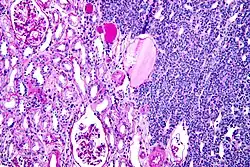

Micrograph of a metanephric adenoma with structures reminiscent of those seen in papillary renal cell carcinoma. H&E stain. | |

Metanephric adenoma (MA) is a rare, benign tumour of the kidney, that can have a microscopic appearance similar to a nephroblastoma (Wilms tumours),[1] or a papillary renal cell carcinoma.

Metanephric adenoma is diagnosed histologically. The tumours can be located at upper pole, lower pole and mid-hilar region of the kidney; they are well circumscribed but unencapsulated, tan pink, with possible cystic and hemorrhagic foci. They show a uniform architecture of closely packed acinar or tubular structures of mature and bland appearance with scanty interposed stroma.[3][4][5][6][7] Cells are small with dark staining nuclei and inconspicuous nucleoli. Blastema is absent whereas calcospherites may be present. Glomeruloid figures are a striking finding, reminiscent of early fetal metenephric tissue. The lumen of the acini may contain otherwise epithelial infoldings or fibrillary material but it is quite often empty. Mitoses are conspicuously absent.[3][4][5][6][7] In the series reported by Jones et al. tumour cells were reactive for Leu7 in 3 cases of 5, to vimentine in 4 of 6, to cytocheratin in 2 of 6, to epithelial membrane antigen in 1 of 6 cases and muscle specific antigen in 1 of 6.[5] Olgac et al. found that intense and diffuse immunoreactivity for alpha-methylacyl-CoA racemase (AMACR) is useful in differentiating renal cell carcinoma from MA but a panel including AMACR, CK7 and CD57 is better in this differential diagnosis.[8] Differential diagnosis may be quite difficult indeed as exemplified by the three malignancies initially diagnosed as MA that later metastasized, in the report by Pins et al.[9]